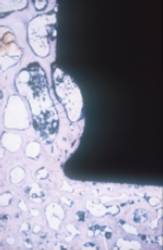

Abb. 20

Oberfläche eines explantierten Titanschaftes (Ti) mit darauf angewachsenem, neu gebildetem Knochengewebe (B)

Abb. 21

Biologische Verankerung einer Pfanne: links die rauhe Titanoberfläche (Ti), rechts der aufgewachsene Knochen (B)

Auch bei der Titanpfanne kann somit eine ähnliche Einbautendenz durch körpereigenes Knochengewebe wie beim Schaft gesehen werden.